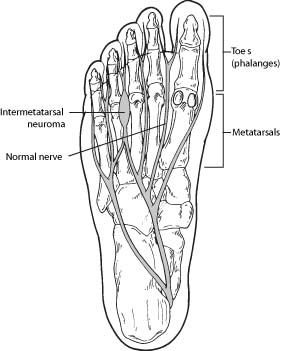

A neuroma is a thickening of nerve tissue that may develop in various parts of the body. The most common neuroma in the foot is a Morton’s neuroma, which occurs between the third and fourth toes. It is sometimes referred to as an intermetatarsal neuroma. “Intermetatarsal” describes its location in the ball of the foot between the metatarsal bones. Neuromas may also occur in other locations in the foot.

The thickening, or enlargement, of the nerve that defines a neuroma is the result of compression and irritation of the nerve. This compression creates enlargement of the nerve, eventually leading to permanent nerve damage.